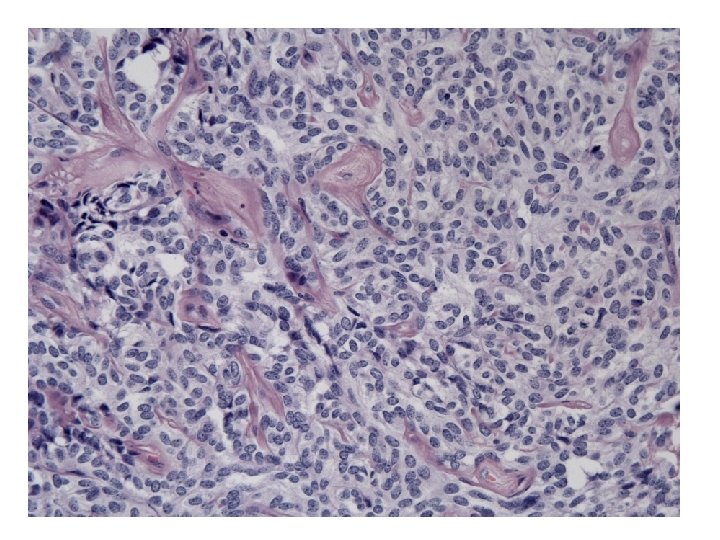

• Some tubular structures: Sertoli? Sertoli-Leydig ?

• Some tubular structures: Sertoli? Extremely rare, all are small and entirely composed of tubules Sertoli-Leydig ? No Leydig cells!

• Looks sex-cord stromal • Looks like rete ovarii • With intraluminal thick eosinophilic secretions

Microscopy • Growth patterns: - Cystic or sieve-like (with eosinophilic secretions) - Tubular - Solid (sheets of cells or closely packed tubules) • Cells: - Epithelioid to fusiform - Pale to eosinophilic cytoplasm • Nuclei: - Round to oval with uniform chromatin - No or few mitotic figures